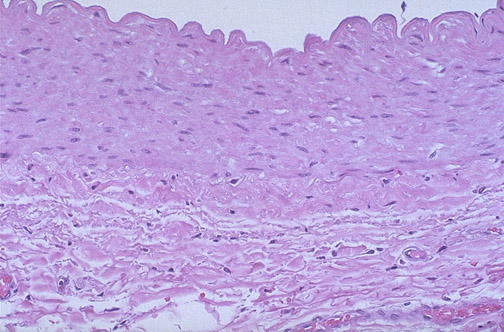

| Distally, major branches of the coronary artery bifurcate to small branches. This is a muscular artery demonstrating a thin intima on top of the internal elastic lamina. Below this is the media with smooth muscle and the external elastic lamina. Outside the media is the adventitia which merges with surrounding connective tissue. |